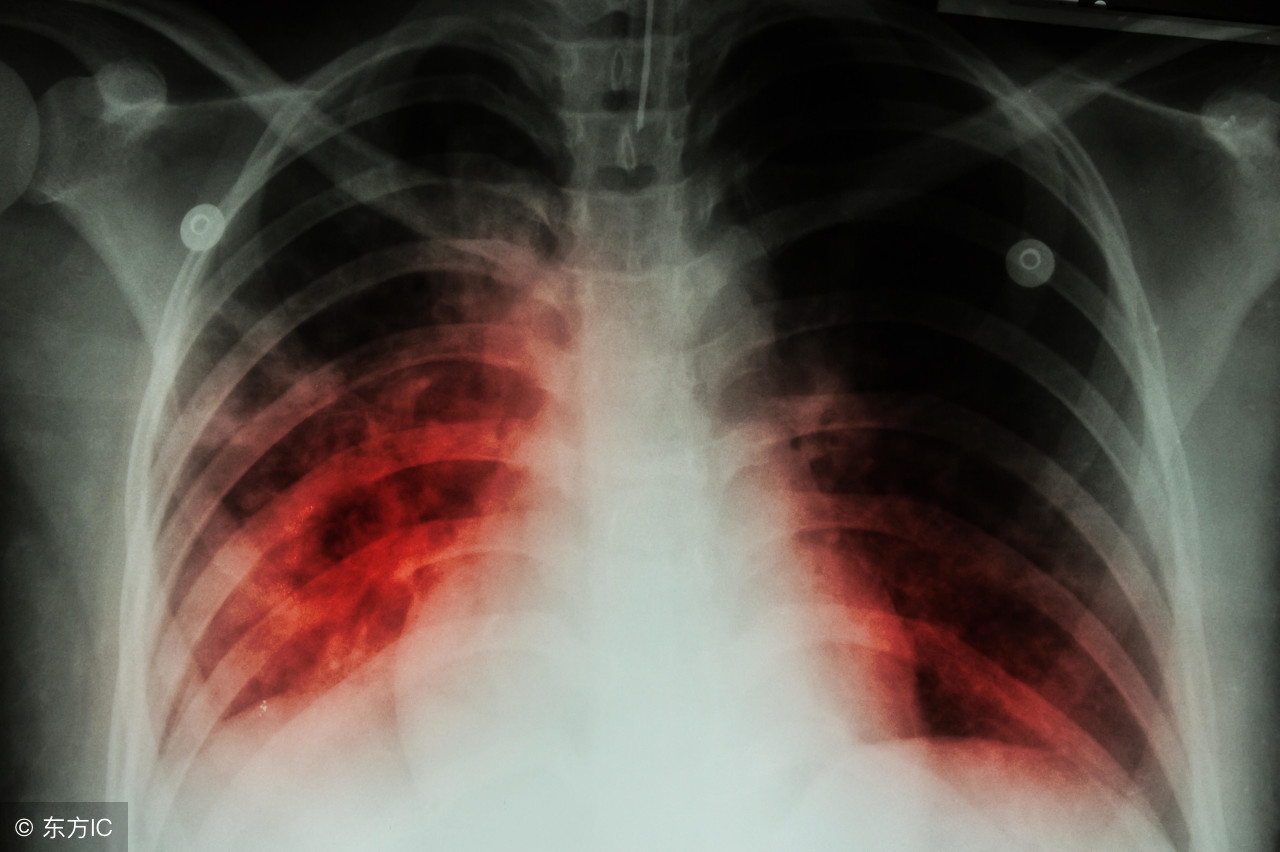

肺大疱性肺气肿是肺气肿的一种,一般认为是局限性肺气肿,是肺大疱和肺气肿的并发情况。原理就是,由于患者肺部肺泡的高度剧烈膨胀以至于最后导致破裂,肺泡壁之间因此相互融合在一起而最终形成了肺大疱性肺气肿。

一般来说,肺大疱性肺气肿的患者容易出现胸口发闷、气短甚至呼吸困难、胸口疼痛甚至内出血的症状。但比较特殊的是,有一些患者,虽然经医生确诊为肺大疱性肺气肿,但是如果他们没有以上这些临床表现,就不需要接受相关治疗。